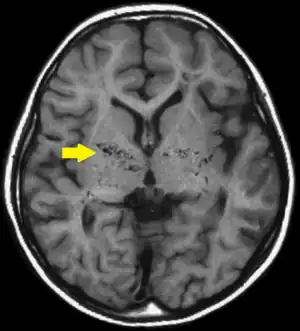

![]() | |

| T1-weighted MR image of moyamoya disease. Flow void in the basal ganglia is indicated by the arrow. | |

Moyamoya disease is a disease in which certain arteries in the brain are constricted. Blood flow is blocked by constriction and blood clots (thrombosis).[1] A collateral circulation develops around the blocked vessels to compensate for the blockage, but the collateral vessels are small, weak, and prone to bleeding, aneurysm and thrombosis. On conventional angiography, these collateral vessels have the appearance of a "puff of smoke" (described as "もやもや (moyamoya)" in Japanese).[1]